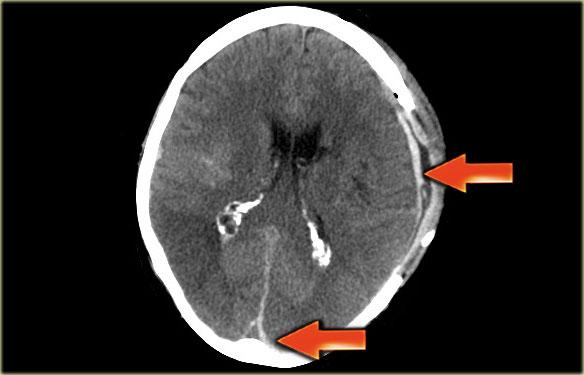

Dấu hiệu delta rỗng giả (Pseudo empty delta sign)

Đây là hình ảnh một bệnh nhân có khối máu tụ dưới màng cứng bên trái, lan rộng đến vùng xoang dọc trên (các mũi tên).

Thoạt nhìn, hình ảnh này trông giống như dấu hiệu delta rỗng.

Khi duyệt qua toàn bộ tập dữ liệu, có thể thấy rõ đây là phần lan rộng của khối máu tụ.

Đôi khi, một ổ mủ màng não (empyema) tăng tỷ trọng cũng có thể bắt chước dấu hiệu delta rỗng.